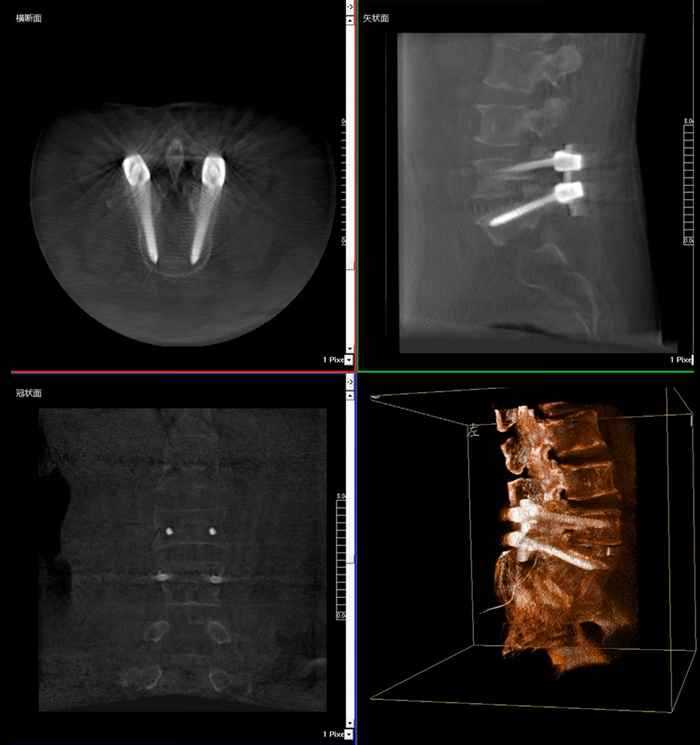

術中三維影像

而三維影像的MPR圖像組可以通過不同平面的切分,使成像區內更豐富的信息得以呈現。尤其是二維影像無法涉及的橫斷面,提供了另一個空間維度的信息量。

在MPR圖像中,冠狀面、矢狀面和橫斷面的信息大大提高了醫生對于病灶區以及手術效果的判定。